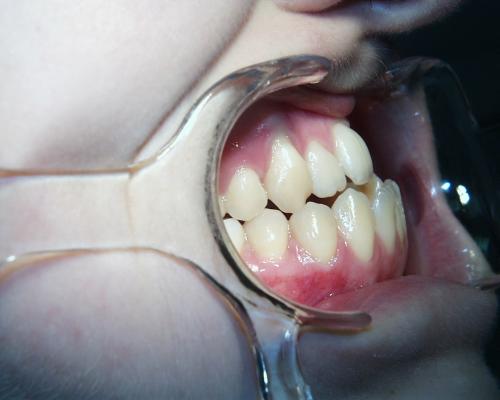

Während der Behandlung

Linkes Bild kurz vor, rechtes Bild kurz nach der Operation. Häufig ist noch eine weitere Anpassung der Zahnbögen und eine Feineinstellung der Verzahnung notwendig. In der Regel müssen die Patienten zwischen den Zahnreihen kleine Gummiringe einhängen, um die Kiefer in der gewünschten Position zu halten.